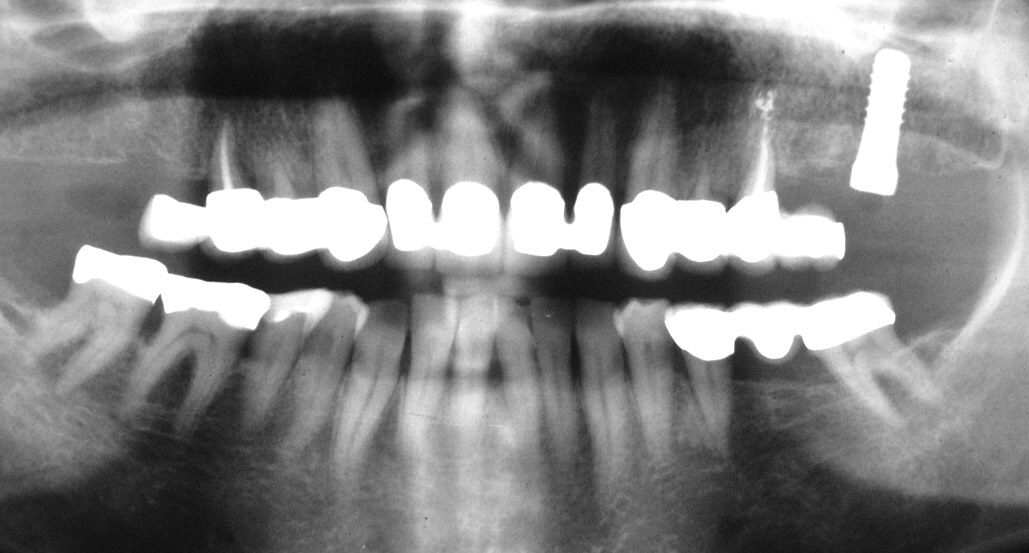

Präprothetisches Ausgangs-OPT im Juni 1991 (Klick!)

Die relativ junge Patientin stellte sich damals mit einem Abszess in regio 17/18 vor. Der gesamte Oberkiefer sah damals schon nicht gut aus. Typischer Röntgen-Befund einer starken Bruxerin (Ein-Blick-Diagnose) mit passender psychosozialer Anamnese. Heute würden wir so einen Fall sicher ganz anders angehen (sofortige Ex der beiden OK-Achter, sofortige EKR der beiden OK-Brücken mit WF nach sorgfältiger Desinfektion von 17, 15 25 und 27), sofortige Neuversorgung mit jeweiliger Verblockung inklusive der Vierer, wenn nicht sogar der Dreier, usw.) und hätten so den 17 und 27 sicher langfristig erhalten und die Erzeugung von Freiendsituationen mit an Sicherheit grenzender Wahrscheinlichkeit  genau so langfristig vermeiden können. Aber damals waren wir noch so herrlich jung und unerfahren, und es handelte sich darüber hinaus ja auch um eine Bekannte....... Deshalb haben wir damls aus heutiger Sicht leider nur die rechte Seite neu versorgt, auf der die Beschwerden aufgetreten waren.

Immerhin hatten wir schon begriffen, welche fatalen Folgen "schlechte Gewohnheiten" in einem menschlichen Gebiss haben können, hatten bereits gelernt, ihre in einem solchen Fall aus unserer heutigen Sicht offensichtlichen Zeichen richtig zu deuten, hatten bereits Erfahrung mit den Segnungen der Timbuktu-Methode  (schauen Sie einmal, wie sich die Situation am 15 über die Jahre gehalten, bzw. sogar trotz des Freiendbrückengliedes verbessert hat) und - das war wohl das Wichtigste- hatten der Patientin plausibel machen können, wie essentiell das konsequente Tragen einer Aufbissschiene ist, wenn man unter dieser Grunderkrankung leidet, nichtsdestotrotz aber seine Zähne erhalten möchte.